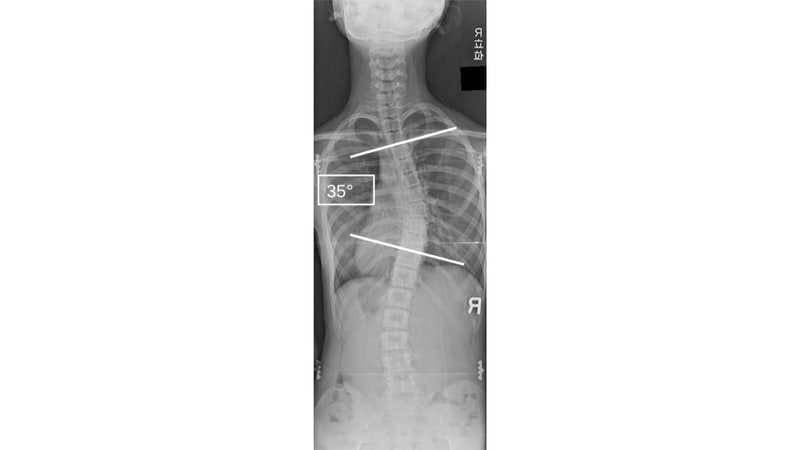

思春期特発性側弯症の症例の背部から撮像したレントゲン(10歳台 女性 コブ角35°の中等症)